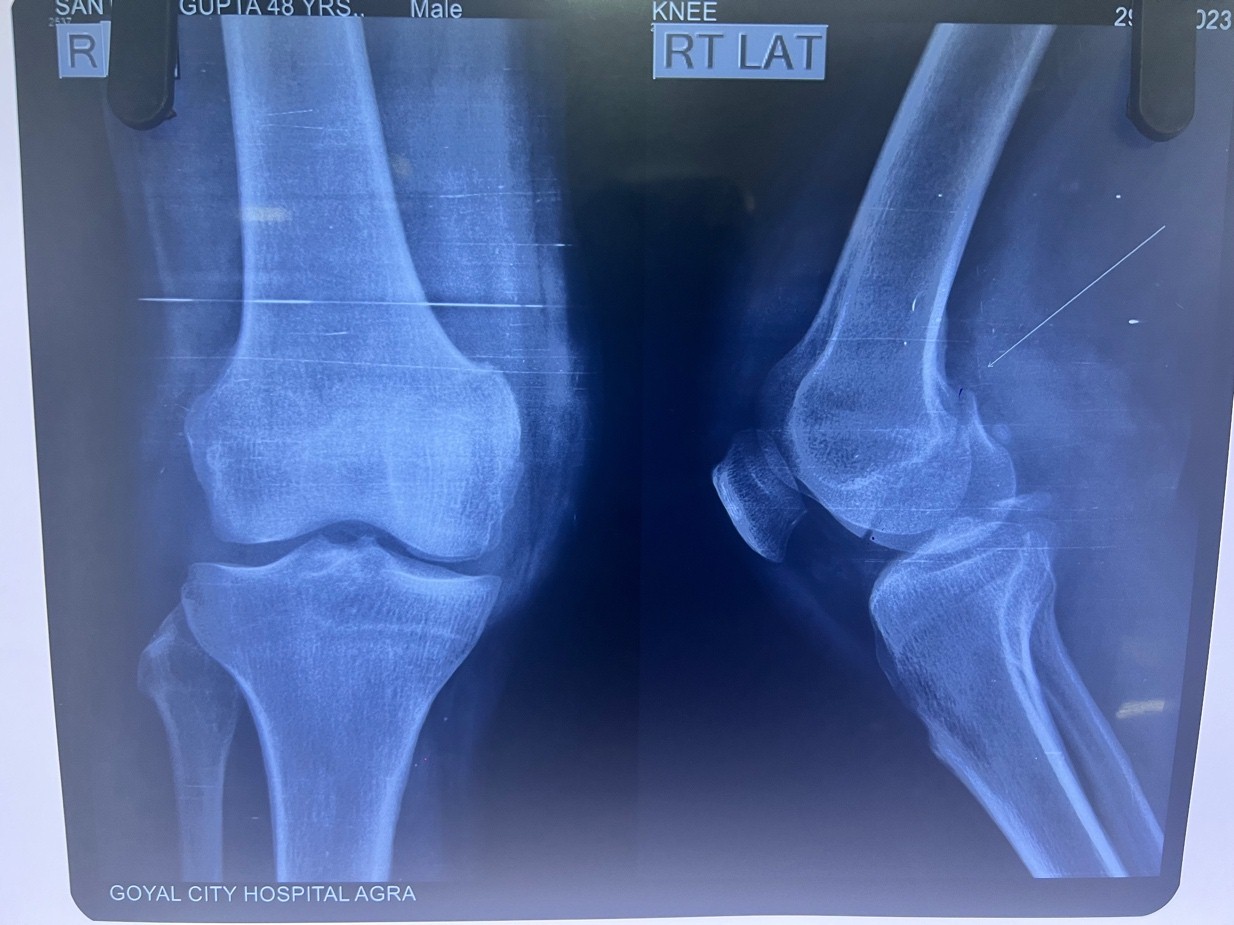

A 48-year-old male presented to the emergency department following a motor vehicle accident with complaints of severe pain, swelling, and inability to bear weight on his left lower limb. On examination, there was significant swelling around the knee joint with marked tenderness over the medial femoral condyle. The patient was unable to perform active knee flexion or extension. Distal neurovascularity was intact. Initial radiographs revealed a coronal plane fracture of the medial femoral condyle, consistent with a Hoffa fracture. In addition, a displaced PCL avulsion fracture was seen (Fig. 1).

Figure 1: Pre-operative X-rays showing a medial Hoffa fracture with the posterior cruciate ligament avulsion fracture.